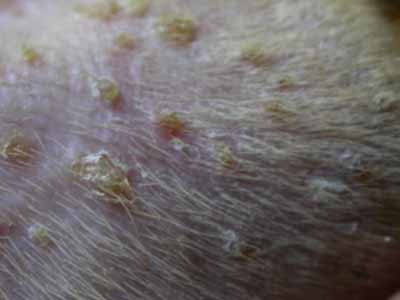

Photo 2 : Atteinte de l’ensemble du corps

©Photo Dr Jacques Lamothe.

Photo 3 : Lésions papulo-pustuleuses en face interne des postérieurs

©Photo Dr Jacques Lamothe.

Photo 4 : Lésions papulo-croûteuses et discret squamosis pityriasiforme amiantacé

©Photo Dr Jacques Lamothe.

Photo 5 : Lésions papulo-croûteuses excoriées et collerettes épidermiques

©Photo Dr Jacques Lamothe.

Photo 6 : Lésion pustuleuse

©Photo Dr Jacques Lamothe.